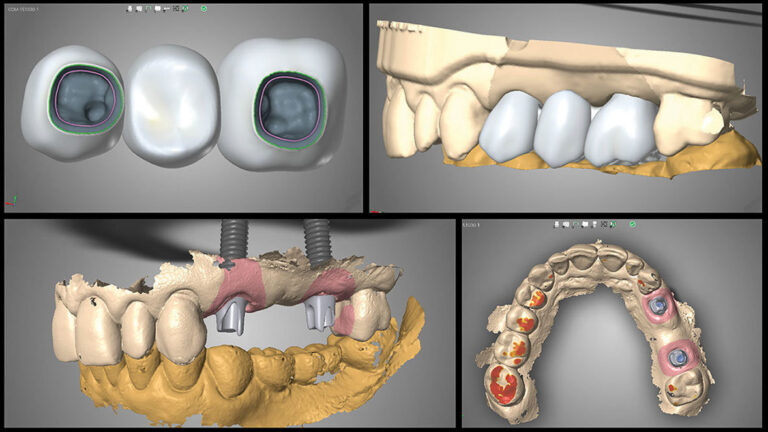

Η τεχνολογία “Δόντια σε Μια Μέρα” επιτρέπει την άμεση αποκατάσταση χαμένων ή κατεστραμμένων δοντιών μέσα σε μία μόνο επίσκεψη στο ιατρείο, χάρη στη χρήση της τεχνολογίας CAD/CAM (Computer-Aided Design/Computer-Aided Manufacturing). Αυτό γίνεται μέσω της ψηφιακής σάρωσης της στοματικής κοιλότητας και της σχεδίασης των αποκαταστάσεων σε έναν υπολογιστή. Τα δόντια κατασκευάζονται άμεσα μέσα στο ιατρείο, χρησιμοποιώντας μηχανήματα που παράγουν απόλυτα προσαρμοσμένες στεφάνες, γέφυρες ή εμφυτεύματα.

Η διαδικασία CAD/CAM περιλαμβάνει τα εξής βήματα:

- Ψηφιακή Σάρωση: Χρησιμοποιώντας έναν τρισδιάστατο σαρωτή, ο οδοντίατρος καταγράφει τη μορφολογία του στόματος σας, χωρίς την ανάγκη για κλασικά αποτυπώματα που είναι πιο άβολα για τον ασθενή.

- Σχεδίαση στο Υπολογιστή: Με τη βοήθεια ειδικού λογισμικού, η προσθετική εργασία σχεδιάζεται με ακρίβεια, λαμβάνοντας υπόψη τις ανάγκες και τις ανατομικές ιδιαιτερότητες του ασθενή.

- Κατασκευή στο Ιατρείο: Τα δόντια κατασκευάζονται επί τόπου από υλικά όπως κεραμικά ή ζιρκόνιο, τα οποία είναι εξαιρετικά ανθεκτικά και αισθητικά άριστα.

- Άμεση Τοποθέτηση: Μόλις η κατασκευή ολοκληρωθεί, τα δόντια τοποθετούνται άμεσα στο στόμα του ασθενή, προσφέροντας γρήγορη και μόνιμη αποκατάσταση.